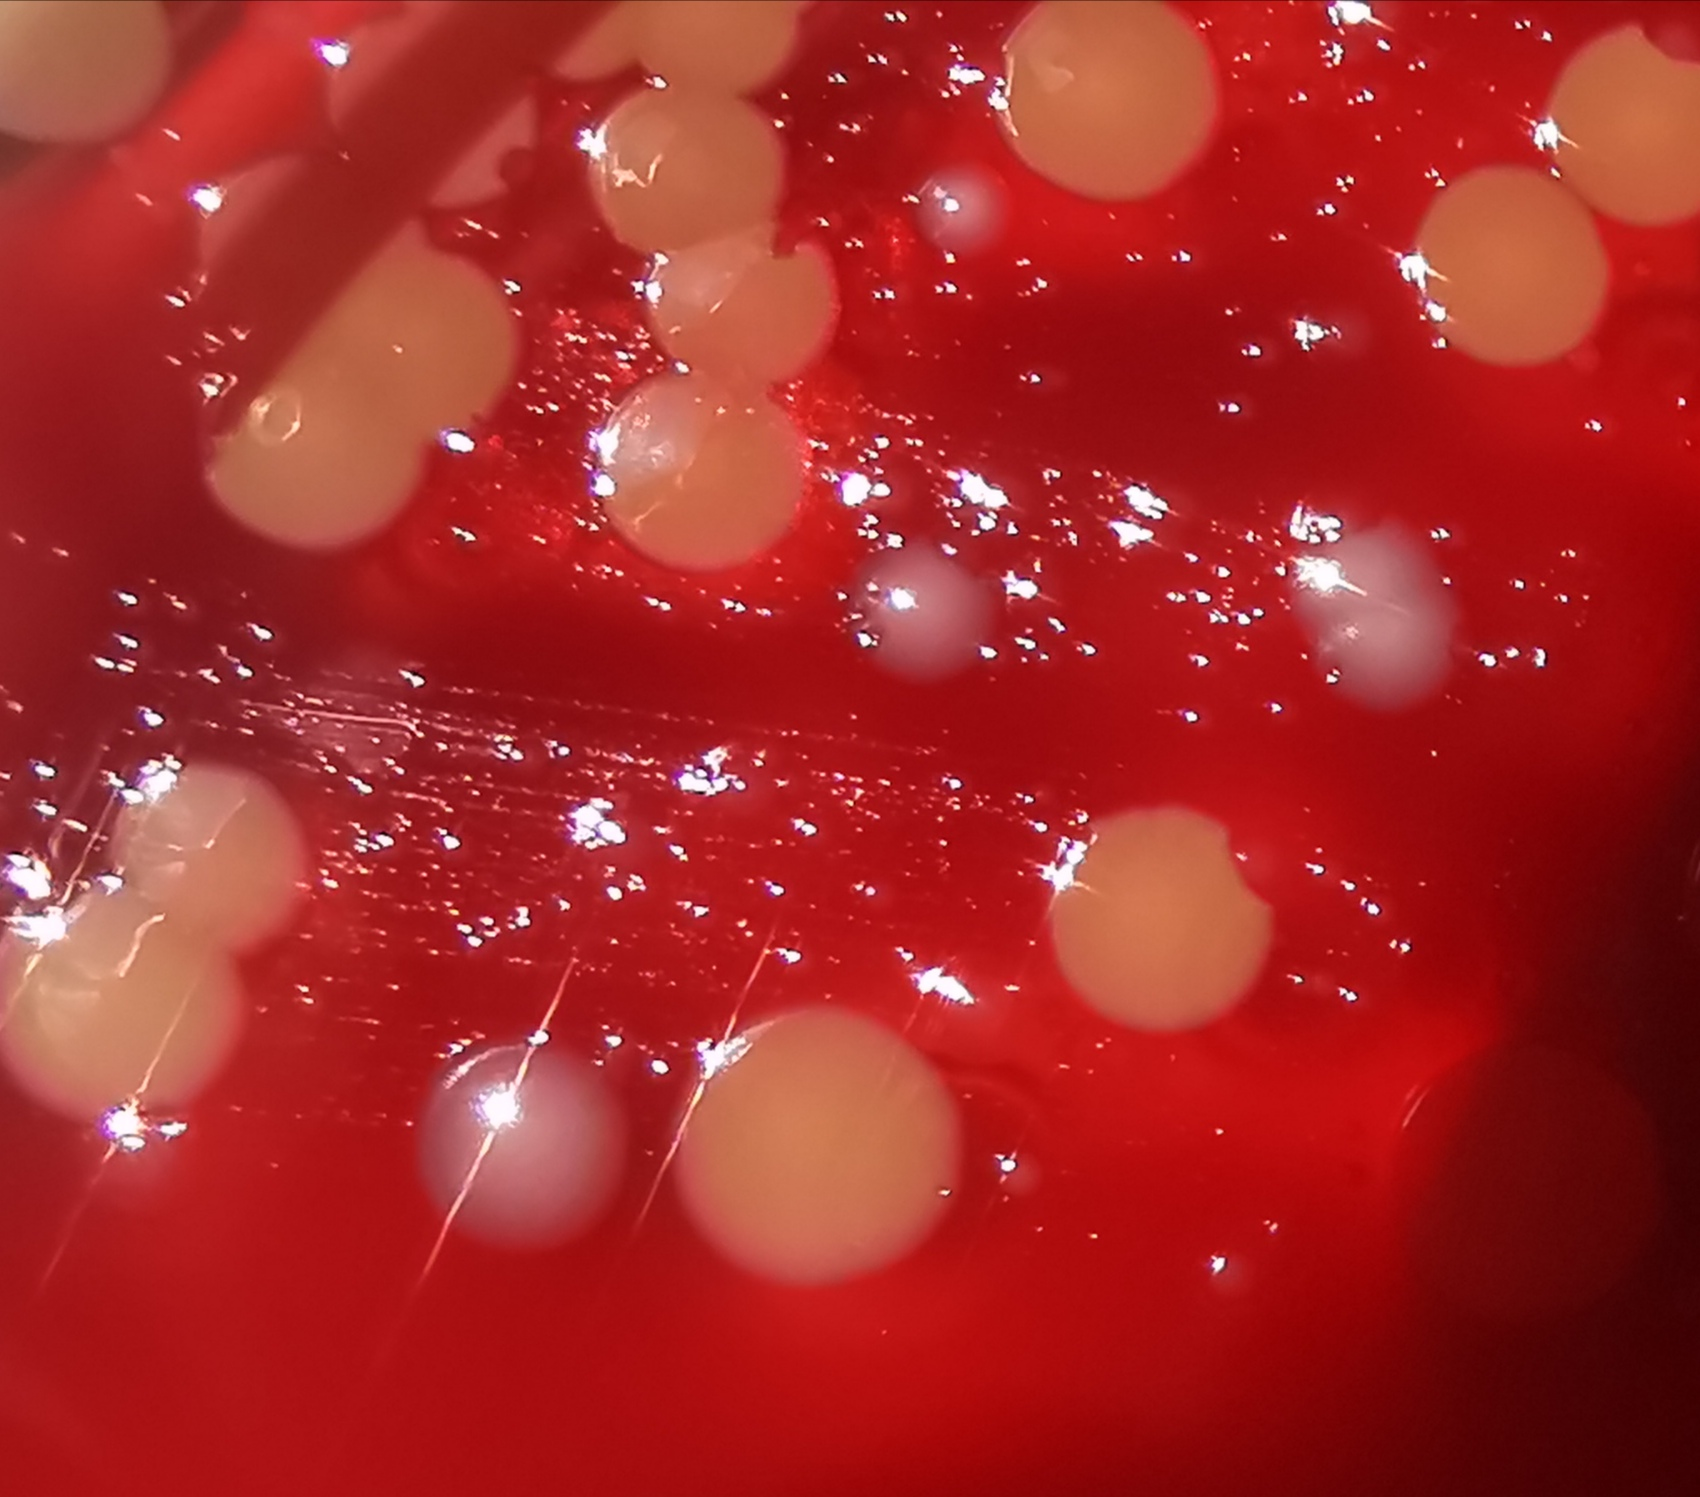

La coltura è il gold standard e i tamponi vanno eseguiti dai siti della sospetta infezione; nel caso di pseudomembrane, il tampone va eseguito sotto la membrana stessa, oppure si può prelevare un frammento di membrana. Il terreno di trasporto dovrebbe essere tipo Amies, addizionato di carbone. La coltura si effettua su agar sangue (di pecora o cavallo), o su agar tellurito. Su agar sangue le colonie possono risultare difficili da riconoscere, a causa soprattutto della scarsa consuetudine di questa osservazione nei Paesi dove la vaccinazione è largamente diffusa: sono colonie convesse, grigiastre e traslucenti (figura 1).

Figura 1. Le colonie grigiastre di Corynebacterium diphtheriae, tra quelle gialline di Staphylococcus aureus, su una piastra di agar sangue (gentile concessione di Alessandro Leonildi, SD Microbiologia batteriologica AOUP)